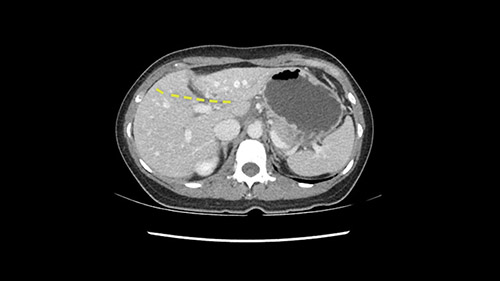

So if we look at the CT scan, on the axial, it’s a larger lesion. It’s about 6 or 7 or 8 centimeters. So it does look a bit threatening in terms of its resectability but if you really drill down deeply into the anatomy, and I think the coronal [imaging] is even better, you can see that the entire mass is on the patient’s left side of the falciform ligament. So it’s really only a left-sided tumor and not even really a left-sided tumor because Segment 4 is uninvolved anatomically.

As I review the CT scan, we have both arterial and venous phases, the tumor is obvious. But I’ll start by saying that the liver itself does not appear to be cirrhotic to my eye. It’s got a normal contour and allied to that, that I do not see evidence of portal hypertension. The spleen is normal, there’s no collateral vessels. The tumor itself, I measured maximally at about 11 centimetres in diameter and I’m told the alpha fetoprotein is very high (over 10000), which is entirely consistent with this being a solitary hepatocellular carcinoma that is very exophytic. It seems to emanate off the inferior margin of Segment 3 (because that’s the falciform). I’ll start by saying that this is not transplantable. The tumor exceeds our guidelines for transplantation, but it's likely resectable based on normal liver and no portal hypertension.

So the issue with regards to resection. A left sided tumor. I believe I can see the falciform ligament right here so we’re looking at a resection of Segments 2, 3 of the left lobe of the liver. The left portal vein is right there. I think we’ll be wiser to take the left portal vein and therefore get well into Segment 4 and do a left hemihepatectomy. Certainly, one does not need to take the middle hepatic vein; it’s miles from the tumor.

Now let’s look at some specific anatomical points for planning this surgery. First thing you see when you see a left hemihepatectomy is that where is the left portal vein and the right portal vein branching? And what is the stump of the left portal vein available for you for ligation? In this particular case, you’ll find that there’s overhanging of the tumor but left portal vein pedicle is sufficiently available for us for ligation.